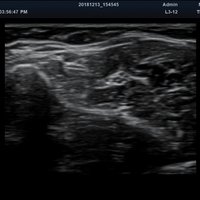

Das Alpinion minisono ist ein tragbares Hand-Ultraschallgerät, das eine sichere und schnelle Diagnostik u. a. in den Anwendungsbereichen Abdomen, MSK, Vaskulär, kleine Organe sowie Bauch und Brust bietet. An das minisono kann über USB-Kabel entweder eine Linear-Sonde oder eine Konvex-Sonde angeschlossen werden. Die komplette ultraschallspezifische Hardware ist in den Griffstücken integriert.

Anwendungsbereiche Abdomen MSK, Nerven, Karotis, periphere Gefäße, Schilddrüse, Mamma

Bildgebungs-Modi B-Modus, CF, M, PW, PD B-Modus, CF, M, PW, PD

• B-Modus: Darstellung zweidimensionale Bilder anatomischer Strukturen